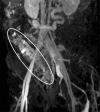

The aim of this study was to identify the frequency of rectosigmoidal involvement in patients with venous malformations (VM) of the lower extremities and to demonstrate multidisciplinary therapeutic options. The medical records and magnetic resonance images (MRI) of patients with VM of the lower extremities, over a six-year period, were reviewed retrospectively in order to determine the occurrence of rectosigmoidal involvement. Vascular interventions, surgical treatments, percutaneous and hybrid (endoscopy-guided angiography) sclerotherapy and procedural complications (according to Clavien-Dindo classification) were also noted. Of the 378 patients with vascular malformation of the lower limbs, 19 patients (5%) had documented venous rectosigmoidal malformation. All of these 19 patients reported episodes of rectal bleeding, while seven patients (36.8%) also had anemia. All patients underwent endoscopy. By endoscopy, seven patients (36.8%) showed discreet changes, and 12 patients (63.2%) showed pronounced signs of submucosal VM with active (47.3%) or previous (15.7%) bleeding. Treatment was performed in all patients with pronounced findings. Six patients underwent endoscopy-guided hybrid sclerotherapy, one patient underwent endoscopic tissue removal, one patient received percutaneous sclerotherapy and one patient received a combination of transvenous embolization and hybrid sclerotherapy. Three patients required open surgery. No complications occurred after conservative treatments; however, one complication was reported after open surgery. None of the treated patients reported further bleeding and anemia at the end of the follow-up period. In this cohort, rectosigmoidal VM occurred in 5% of patients presenting with a high incidence of rectal bleeding. Percutaneous or endoscopy-guided hybrid sclerotherapy appeared to be a safe and effective alternative to surgery.